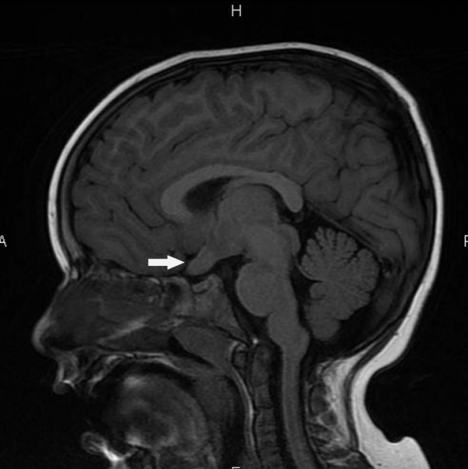

1型神经纤维瘤病(NF1)是人类常见的遗传疾病之一。它是由17号染色体上NF1基因的突变引起的,并与许多中枢和周围神经系统表现有关。患有NF1的儿童较有可能出现许多可能需要神经外科医生注意的病变。其中一些包括视神经神经胶质瘤,脑积水,脊柱内肿瘤和周围神经瘤。尽管影响儿童大脑,脊柱和外周神经的大多数肿瘤是低度病变,但仍有很小但的风险,即随着时间的流逝,其中一些病变可能会变成高度病变,需要单独进行手术以外的其他治疗方式。

儿童期NF1可能导致的其他相关疾病包括I型Chiari畸形,脊柱侧弯,由于没有蝶骨翼而产生搏动性眼球突出症。在本综述中,对在NF1儿童中发现的主要病变以及神经外科医生和治疗团队其他成员提供的治疗类型进行了回顾。今天,由神经外科医生,神经科医生,眼科医生,放射科医生,整形外科医生和整形外科医生组成的多学科团队为NF1儿童提供较佳护理。